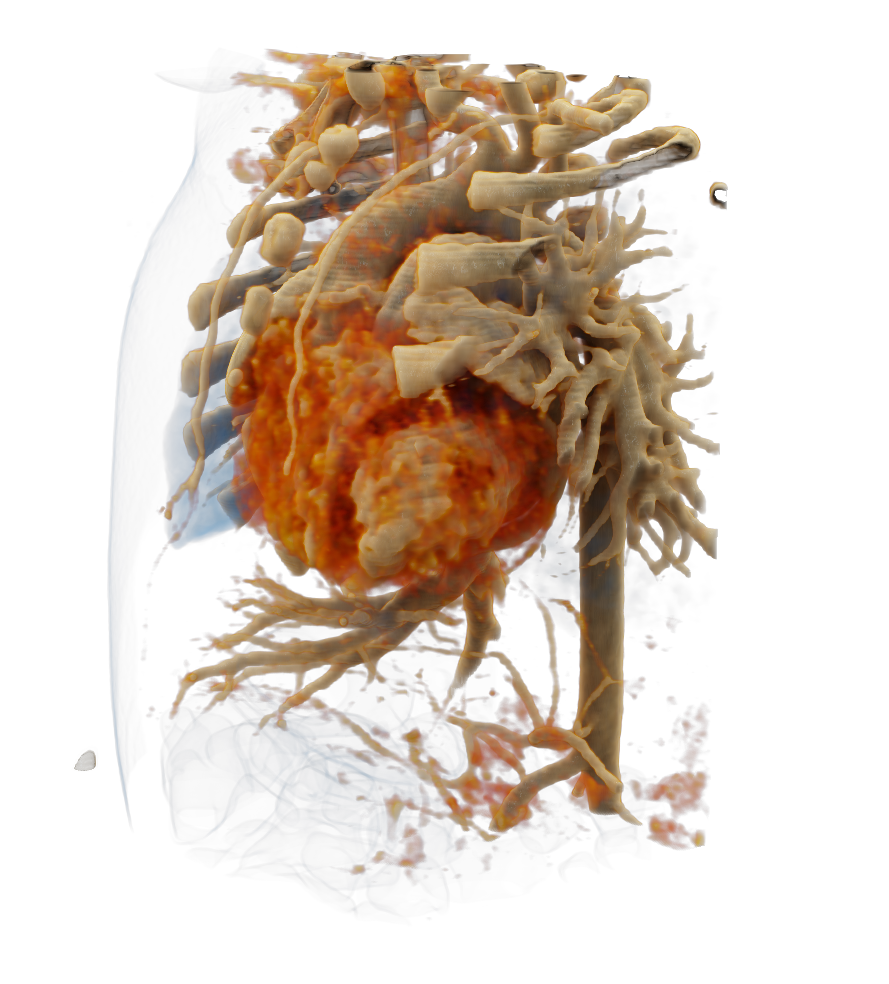

Visualize the smallest structures of the heart realistically without surgery? About the use of a prototype that makes this vision almost tangible.

Cardiac surgery is one of the most difficult procedures, and it gets even more complex when it comes to operating on tiny children’s hearts. Visualization techniques like cinematic rendering provide a detailed 3-D view of the patient’s heart and surrounding anatomy. But what happens when these images are turned into a hologram that can be rotated, zoomed, and looked at from all possible perspectives?